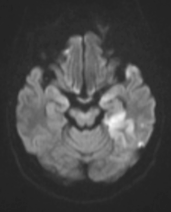

张女士被紧急送往附近医院,头颅磁共振检查明确诊断为急性脑梗死。

神经介入诊疗中心主任、副主任医师刘俊中接诊后,根据各项检查检验结果迅速判断张女士属于颅内大血管病变。

左侧大脑中动脉和颈内动脉均已闭塞,相当于左侧大脑半球几乎断了供血,手术指征明确。

5 分钟后,张女士被推进介入手术室,急诊脑血管造影进一步确认了血管闭塞情况。